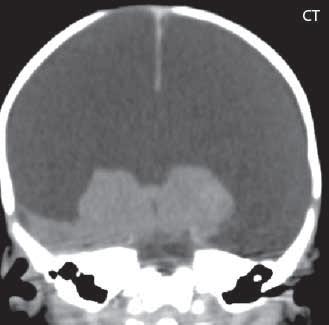

Obr. I.1.2c Ageneze corpus callosum, frontální rohy postranních komor mají tvar rohů na Vikingské helmě, kraniálně uložená III komora

Obr. I.1.2e Ageneze corpus callosum, frontální rohy postranních komor mají tvar rohů na Vikingské helmě, kraniálně uložená

III komora, Probstovy provazce (šipka)